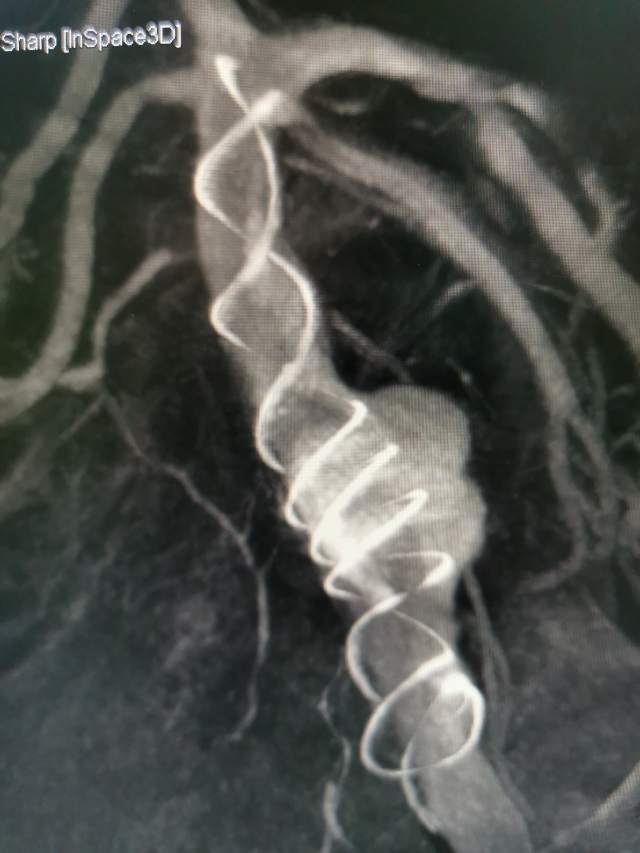

患者男性,34岁,年前自新疆坐车48小时来到我院,诊断:椎基底动脉冗长扩张症,出现脑干压迫症状、后组颅神经症状、部分中组颅神经症状、小脑症状、颅内压增高(220mmHg),症状进行性加重,最大径15mm,血管外面存在血栓造影只能窥见部分,短短两周,病变形态出现明显变化,局部出现明显瘤样凸起(图2-3),手术方案只能临时改变,植入血流导向装置,术后看病人语言、四肢活动均正常,围手术期仍然是一个艰巨的过程,充满了不确定因素,希望患者能安全度过围手术期,早日康复,重返工作岗位~~~